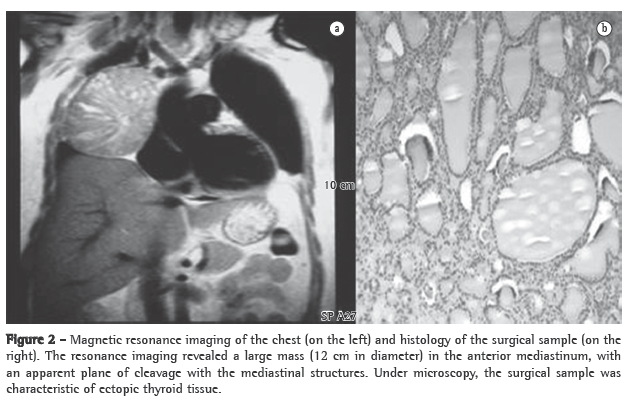

Complementary tests performed in the emergency room revealed normocytic normochromic anemia (hemoglobin, 11.3 mg/dL; mean globular volume, 86.8 fl; and mean corpuscular hemoglobin, 33.7 mg/L), normal total leukocyte counts (7 g/L), hypokalemia (3.3 mmol/L) and hypoalbuminemia (3 g/dL), as well as an increase in the levels of aspartate aminotransferase (60 U/L), alanine aminotransferase (79 U/L), lactate dehydrogenase (196 U/L), alkaline phosphatase (272 U/L) and C-reactive protein (19.2 mg/dL). The patient also presented hypoxemia on room air (PaO2: 79.5 mmHg) and mild hypocapnia (33 mmHg). A chest X-ray revealed opacity in the middle third of the right lung field (Figure 1).

An anteroposterior and lateral right chest X-ray revealed enlargement of the right upper mediastinum.